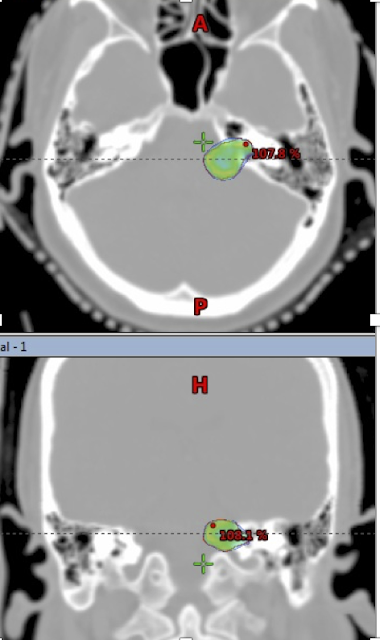

![]() |

| Acoustic Schwannoma (left) outlined in red, in axial and coronal CT images; SRS dose represented by colourwash, closely conforms to the edges of the lesion. |

The most

common schedule is a single fraction of radiosurgery, delivering 11-13 Gy to

the edge of the lesion (and a higher dose centrally). Larger lesions may

however be treated using more protracted schedules, comprising 3, 12 or 28

sessions.